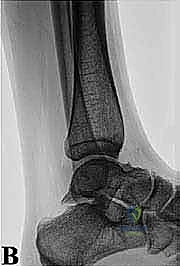

* الأشعة السينية (X-rays): بوضعيات خاصة (Lateral view) لرؤية العظم الزائد (Os Trigonum) والنتوءات العظمية وتضيق المسافات المفصلية.

* التصوير بالرنين المغناطيسي (MRI): هو المعيار الذهبي. يكشف بدقة متناهية عن التهابات الأوتار (مثل FHL)، ارتشاح السوائل، تمزقات الأربطة، ووذمة نخاع العظم (Bone Marrow Edema) التي لا تظهر في الأشعة العادية.

* الأشعة المقطعية (CT Scan): تُستخدم في حالات معينة لعمل خريطة ثلاثية الأبعاد للكسور القديمة أو التكلسات العظمية المعقدة قبل الجراحة.

* استئصال العظم الزائد (Os Trigonum Excision): يتم فصل العظم الزائد بحذر عن الأنسجة المحيطة واستخراجه بالكامل، مما يزيل سبب الانحشار والألم فوراً.